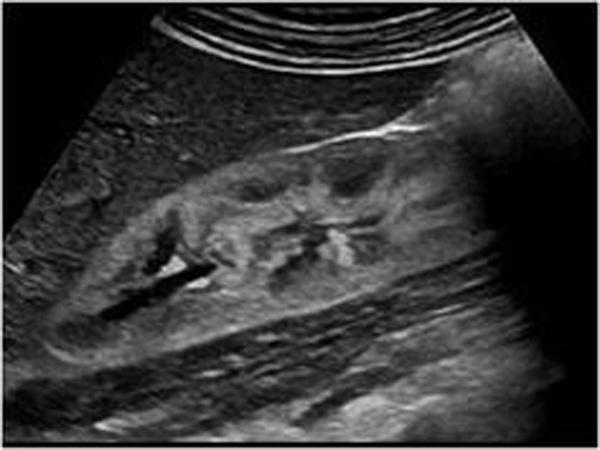

Xanthogranulomatous Pyelonephritis XGPN

Chronic Pyelonephritis due to stone

type of Chronic Pyelonephritis

Xanthogranulomatous Pyelonephritis XGPN

Chronic Pyelonephritis due to stone